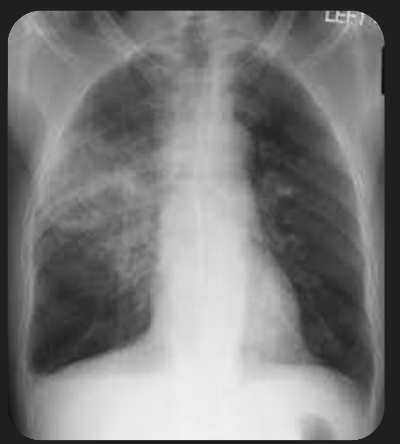

5. 폐렴 증상

폐렴 증상은 질환이 진행되면서 다양하고 심각하게 나타납니다. 주요 증상으로는 고열, 후두통, 가래를 동반한 강한 기침, 흉통, 호흡곤란, 빠른 호흡 등이 있습니다. 가래는 화농성으로 노란색이나 녹색을 띕니다.